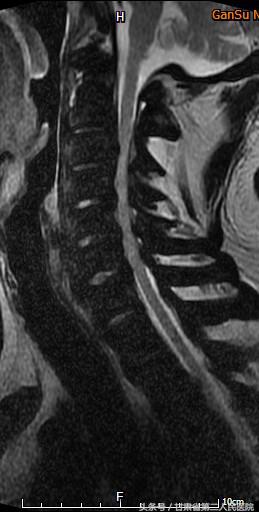

入院后行全脊柱X线、CT及MRI示:C3-6颈椎后纵韧带骨化引起的脊髓型颈椎病,并有严重的石骨症。

可见全身骨质密度均匀增高,符合石骨症表现

术前